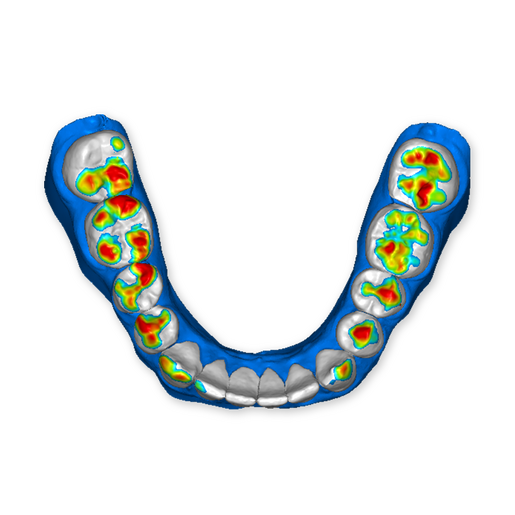

The DSD Interdisciplinary is a digital wax up of the upper and lower arches, designed considering a facially-driven, clinical and functional analysis of the patient.

It is our most comprehensive planning option, and includes all the 3D treatment simulations needed for each case, such as ortho, perio, implants, grafts and orthognathic surgery.

Our 3D simulations showcase various treatment suggestions, facilitating a deeper understanding of the required procedures. This leads to the creation of a broader treatment plan and enables a more efficient communication with your patients.